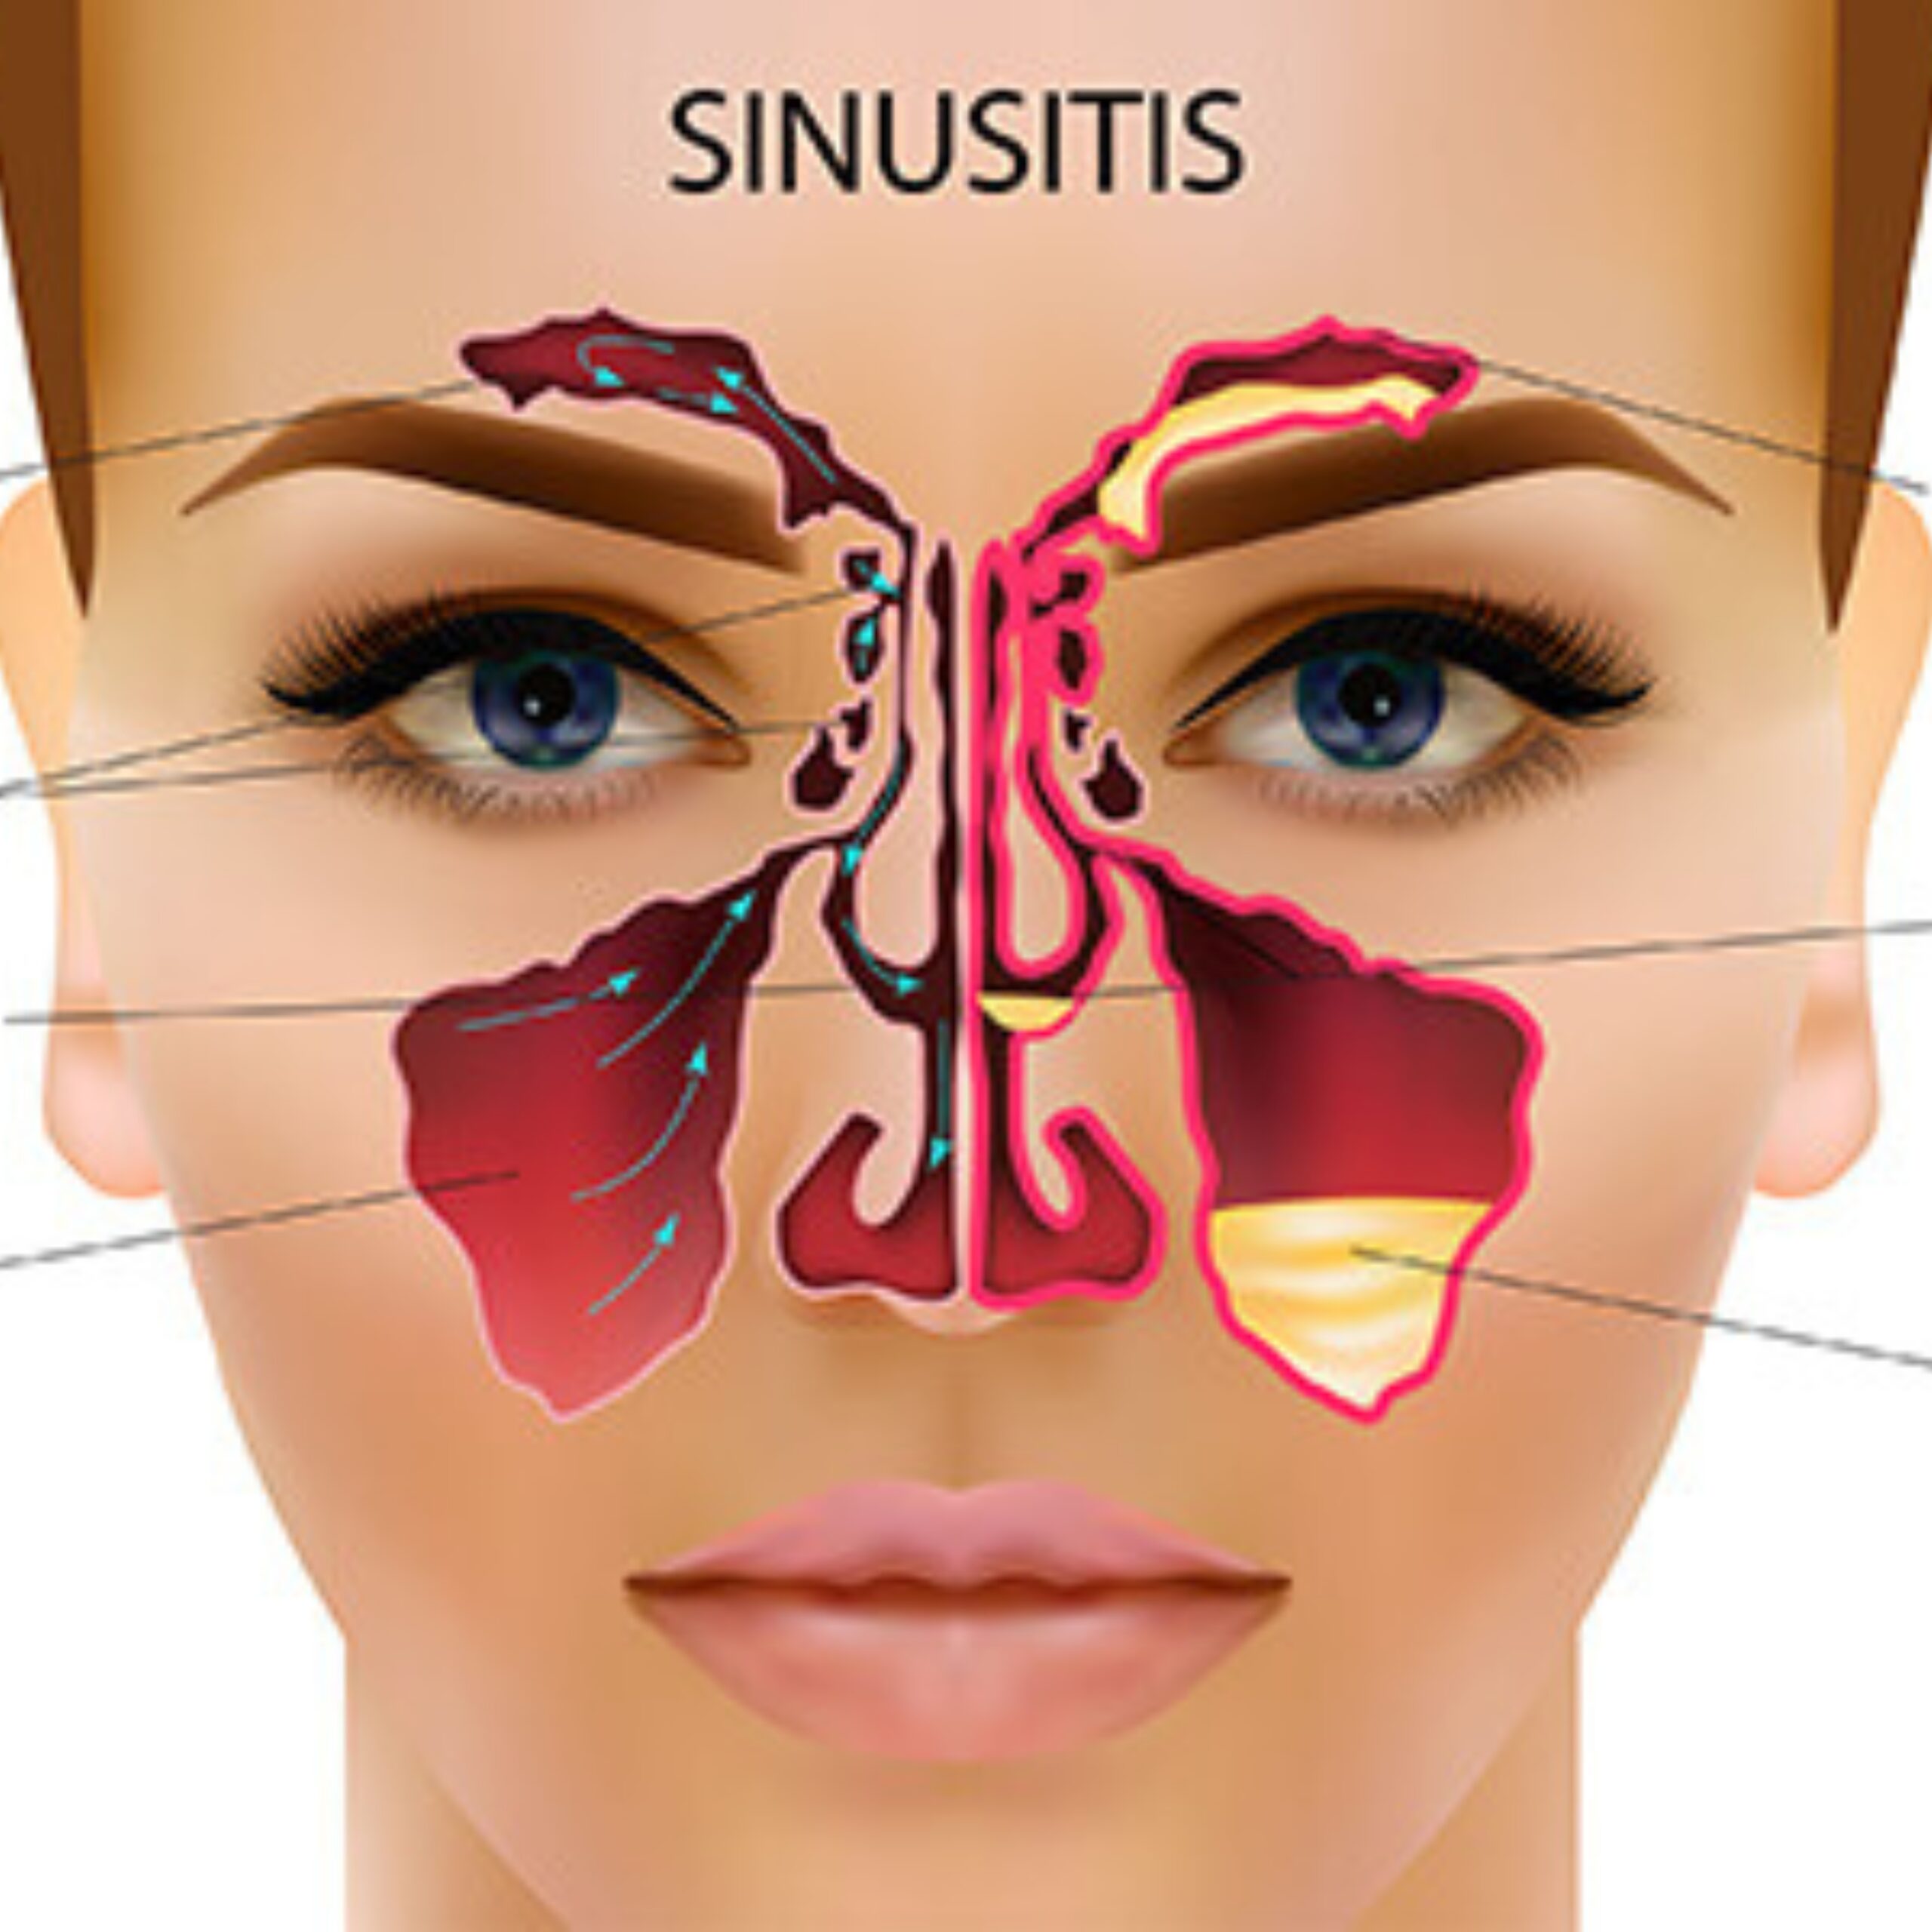

Expert Sinus & Nasal Surgery

Endoscopic solutions for sinus disorders, polyps, and nasal blockages.